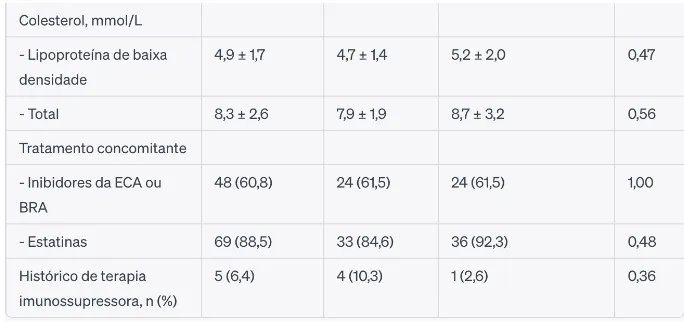

Foram randomizados 78 pacientes (39 para cada grupo). A tabela abaixo apresenta as características de base dos pacientes.